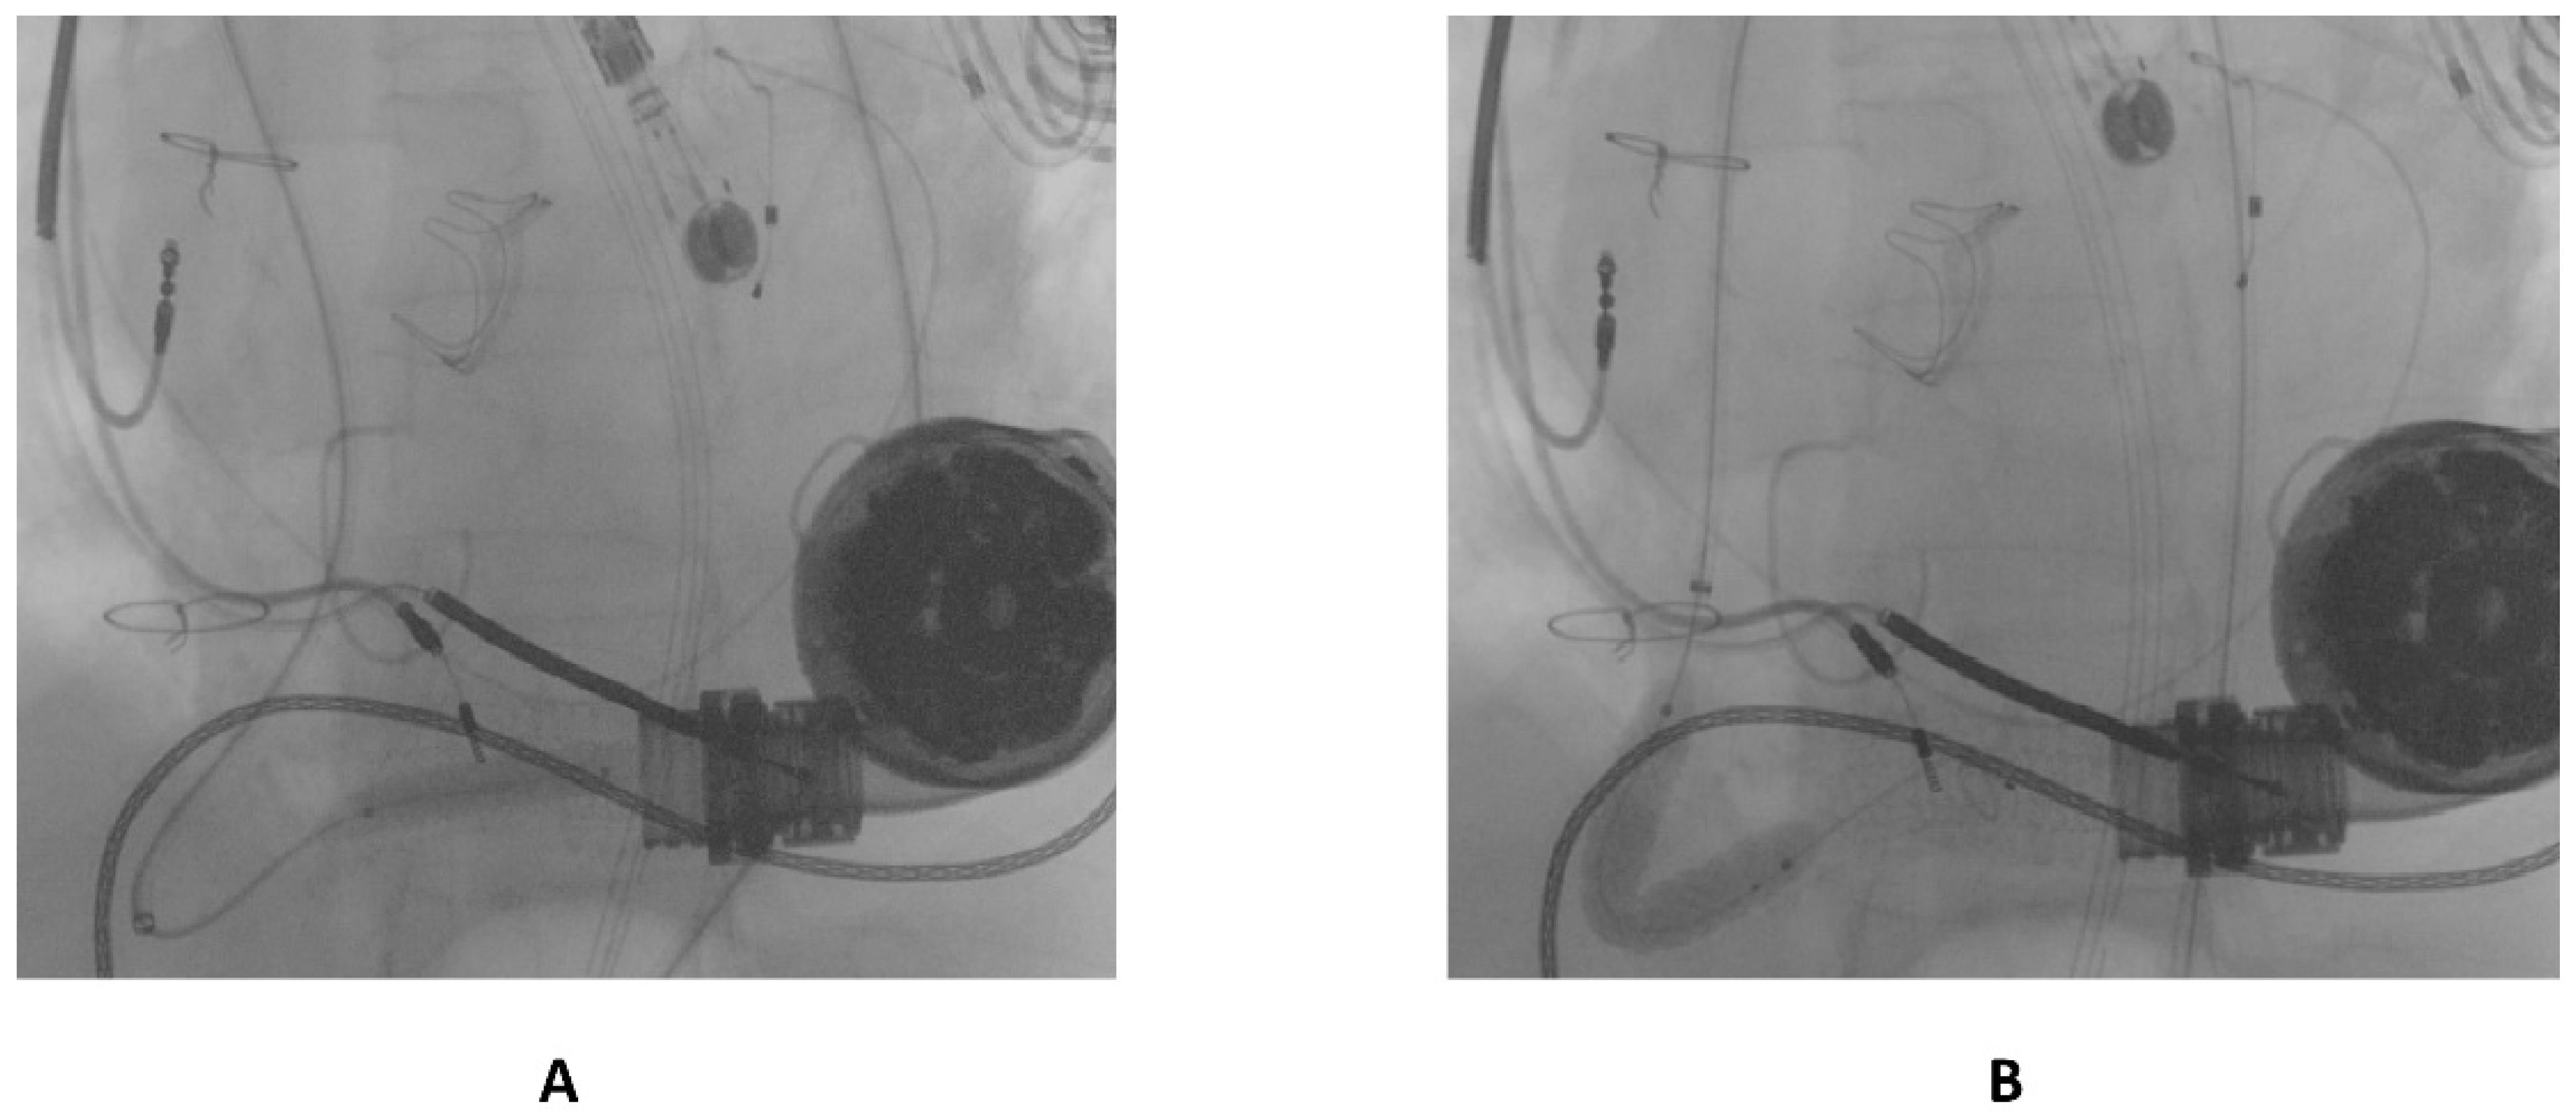

Final angiography showed complete flow restoration and the optimal patency of the stent previously implanted in the proximal segment of the graft 12 months before, as shown in Figure 5.

Figure 5.

Final result following the percutaneous intervention.